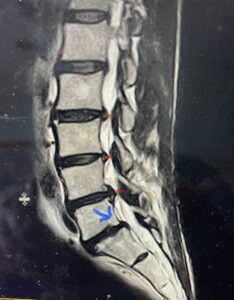

(Fig. 3) lateral intraoperative cervical x-ray demonstrating good alignment after C4-C6 anterior cervical discectomy and interbody fusion with plate. Note the interbody grafts help load-share the plate in this patient with severe osteoporosis

This 59 year-old female had severe bilateral leg pain and numbness over a 6-month period. The patient had failed conservative treatment with physical therapy, chiropractic care, and medications. MRI revealed that she had severe lumbar stenosis with a grade 1 spondylolisthesis or “slipped disc” at L5-S1 (Fig. 2). In addition, she had previously undergone both front and back surgery for severe cervical stenosis where her posterior hardware had failed because of her severe osteoporosis requiring us to remove the posterior hardware. This required her to have an anterior or front operation which allowed better fixation to her spine because of the load-sharing nature of the interbody grafts in addition to her anterior cervical plate (Fig. 3).